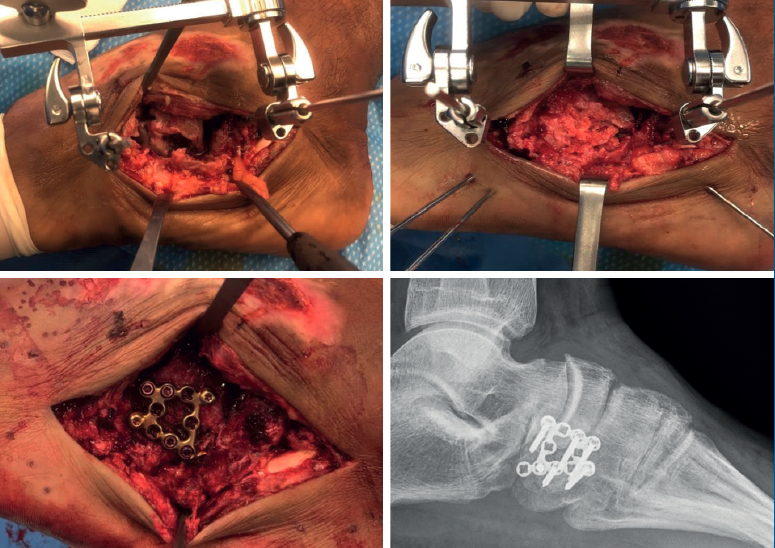

Los 7 pacientes diagnosticados de manera aguda fueron tratados de manera quirúrgica mediante reducción abierta y fijación interna (RAFI). Se usó un fijador externo para distraer la fractura, recuperar la longitud ósea y reducir las superficies articulares. En los casos de conminución metafisaria y defecto óseo se usó aloinjerto de esponjosa. Una vez reducida la fractura, se realizó, en 5 casos, osteosíntesis mediante placa anatómica de cuboides de bajo perfil con tornillos de 2,6 mm y en 2 casos osteosíntesis con agujas de Kirschner de 1,8 mm. En el mismo acto quirúrgico fueron tratadas las lesiones asociadas: reconstrucción y osteosíntesis de las fracturas de calcáneo y escafoides, así como reducción y fijación de la lesión del complejo de Lisfranc y de la luxación de los metatarsianos cuarto y quinto. Solo en un caso fue necesario mantener el fijador externo de manera temporal 6 semanas (Figura 3).

Las opciones para el tratamiento quirúrgico agudo de las fracturas de cuboides incluyen reducción abierta y fijación interna, fijación externa o una combinación de ambas. Entre los objetivos correctivos destaca, en primer lugar, la recuperación de la columna lateral del mediopié, para lo cual es útil la utilización de un fijador externo a modo de distractor que se puede emplear de manera temporal o definitiva, usando auto- o aloinjerto óseo si existe gran conminución metafisaria; en segundo lugar, la reconstrucción de la superficie articular para evitar una artrosis postraumática precoz secundaria a la fractura; y, en último lugar, el tratamiento de las lesiones asociadas, que será individualizado en cada caso. Este gesto ha sido reproducido por otros autores en la literatura, como en el trabajo publicado por Sharma et al.(1); en su serie de 12 casos, abordan el acortamiento de la columna lateral mediante ligamentotaxis y estabilización con fijador externo de manera definitiva en 8 casos y osteosíntesis con agujas de Kirschner en los 4 restantes. Este trabajo aconseja tratar todas las fracturas en cascanueces de cuboides (nutcracker's fracture) en las que exista un acortamiento de la longitud ósea de manera quirúrgica y, en casos de inestabilidad axial persistente después de la reducción y osteosíntesis de la fractura, dejar el fijador externo a modo de distractor temporal durante 6 u 8 semanas, en lugar de recurrir a placas puente estabilizadoras colocadas a través de varias articulaciones(7).